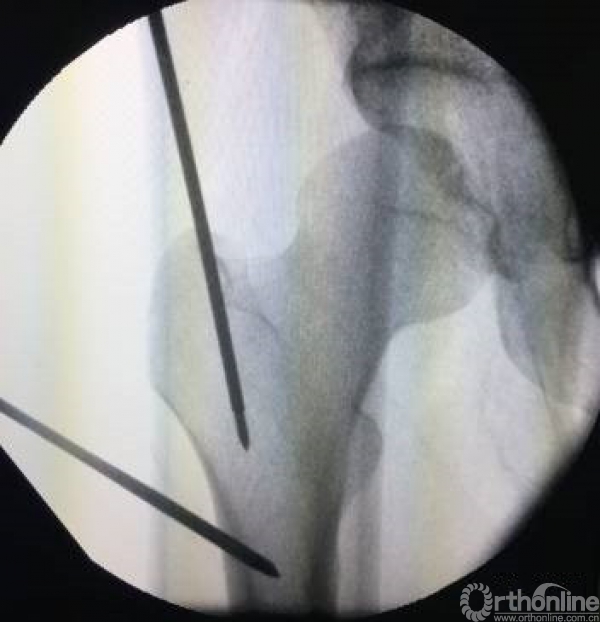

屈髋屈膝牵引入钉可以有效放松股骨近端的肌肉(髂腰肌、臀中肌),从而可以更好的进行骨折复位。尤其是粗隆下骨折

但进钉点不太适合选用梨庄窝进针,同时透视角度也需要进行微调。

最需要注意的就是进针点的选择。

进针点不良会导致复位出现内外翻。

进针点选取的时候,一定注意腿的旋转。以小粗隆为参考,小粗隆稍微重叠1/3时一般为正位。

同时可以对于近端复位不良时,可以采用顶棒纠正前后旋转,克氏针纠正内外旋转。